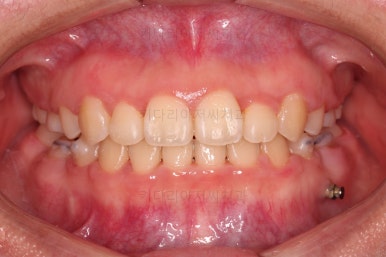

초진 때의 입안 모습입니다.

원래 다니던 치과에서 1년여 교정치료를 진행하신 상태였는데요.

몇 가지 이상한 점이 보이죠?

한 쪽만 발치가 되어있다.

아랫니에 유치가 2개가 그대로 남아있다.(화살표)

몇몇 이아에는 장치가 부착되어 있지 않다.

마찬가지로 초진 시의 얼굴모습이에요.

삐뚤한 앞니로 인해 활짝 못 웃으시는 상태였고, 입을 다물었을 때 돌출감이 느껴졌어요.